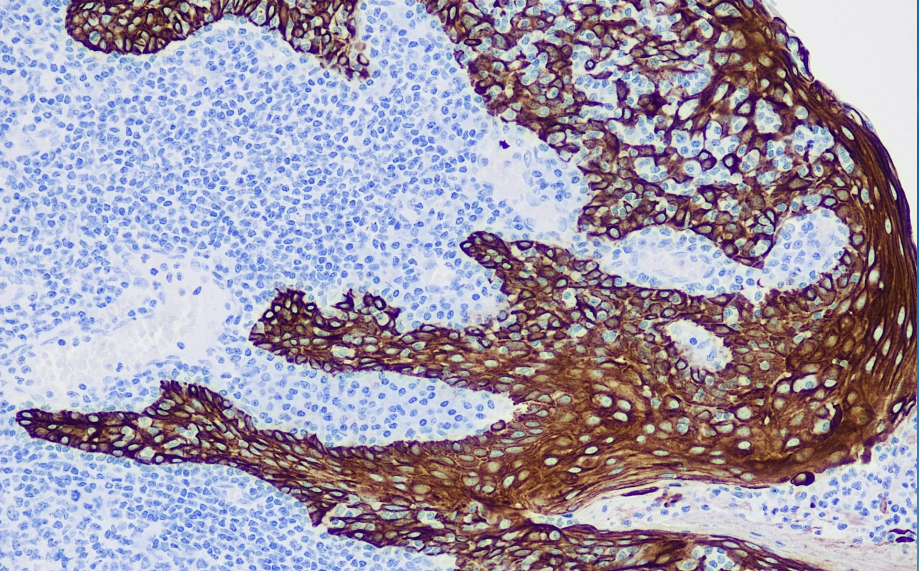

Positive control: tonsils

34 betaE12 is a high-molecular-weight cytokeratin that recognizes human keratin intermediate filament proteins 1, 5, 10, and 14, and is expressed in squamous epithelium, ductal epithelium, and other stratified epithelia. This antibody is expressed in tumors such as lung squamous cell carcinoma, breast cancer, pancreatic cancer, cholangiocarcinoma, and bladder transitional cell carcinoma, but is not expressed in mesothelioma, lymphoma, melanoma, neuroblastoma, and neuroendocrine tumors. This antibody marks myoepithelial cells, and when used in combination with p63, it aids in distinguishing between benign and malignant prostate lesions and benign and malignant breast ductal tumors.

CK34Betaβ E antibody reagents can specifically bind to CK34Betaβ E molecular antigens. Immunohistochemistry kits containing CK34Betaβ E antibody reagents are suitable for the auxiliary diagnosis of lung squamous cell carcinoma, breast cancer, pancreatic cancer, cholangiocarcinoma, benign and malignant prostate lesions, and benign and malignant breast ductal tumors.